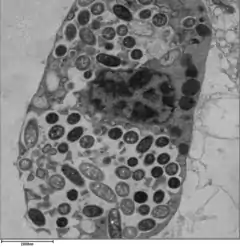

| TEM image of L. pneumophila | |